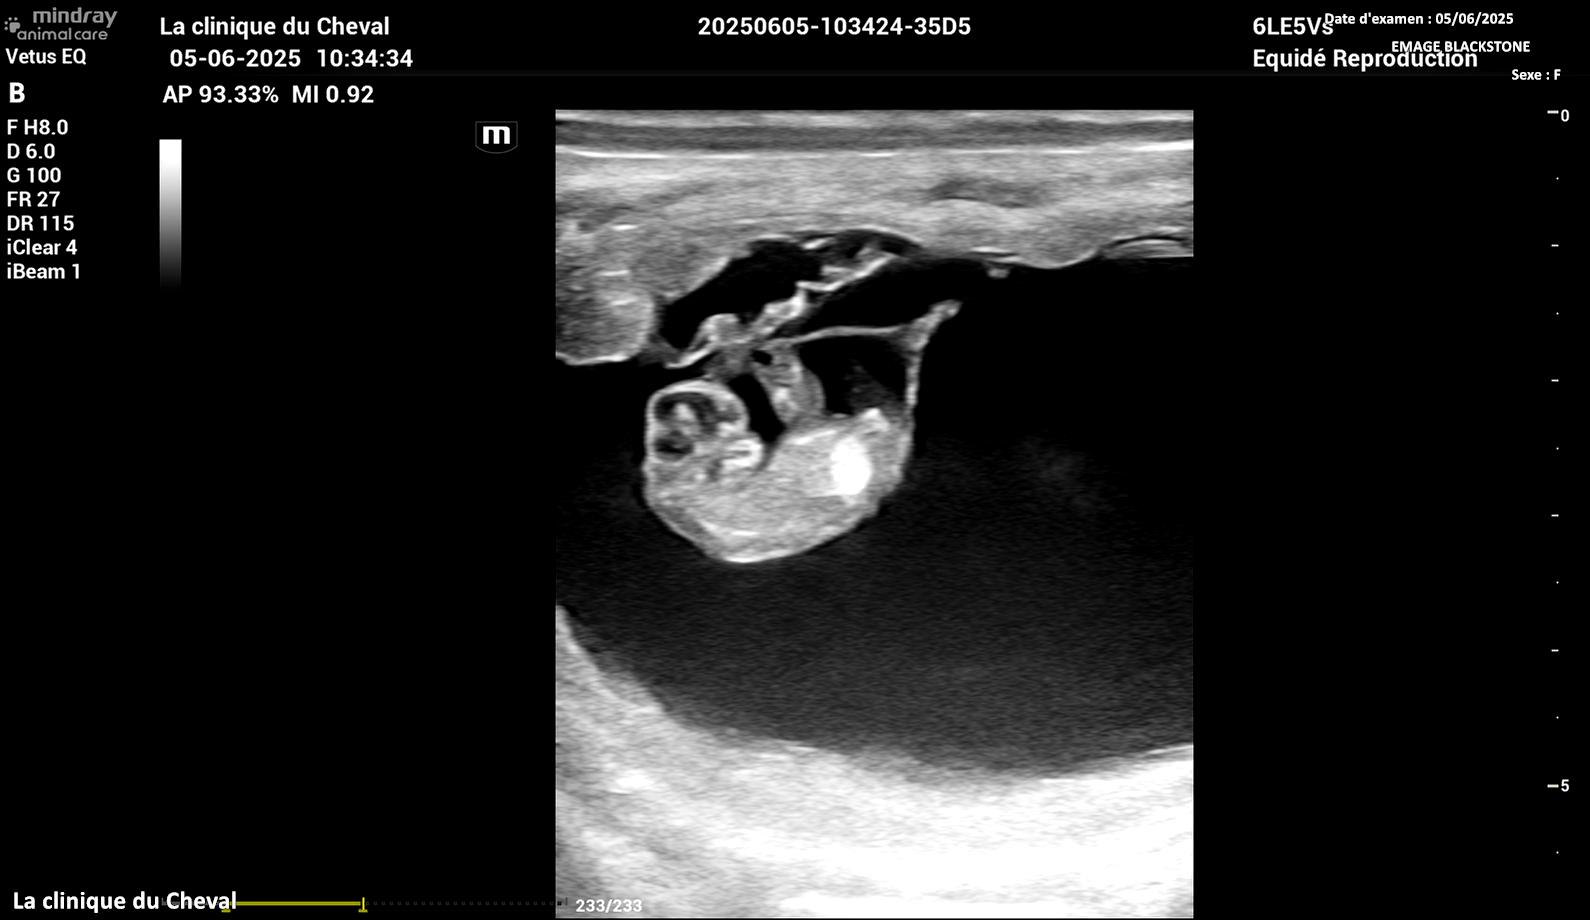

EMAGE BLACKSTONE est bien confirmée pleine à 40 jours

de WESTAIRE TOLOMEO :

plus que 10 mois !